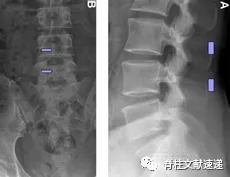

图注:定位椎间隙上下两个椎弓根的下缘,棘突旁开1cm为两个操作区

图注:术中腰椎透视图像关节镜通道与操作通道交汇。